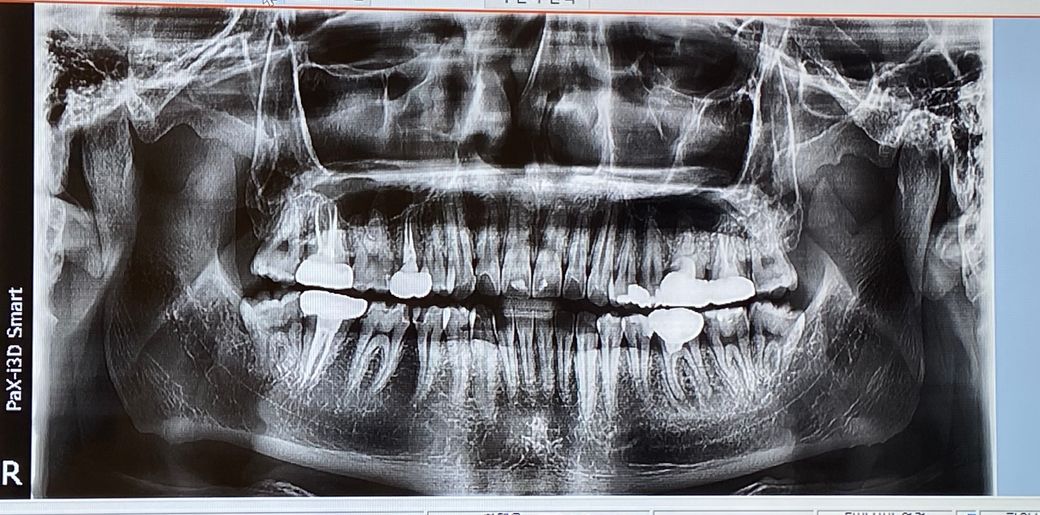

1. 좌측 아래 금니 재신경치료 할것이 있는데 상태 어떤가요? 그리고 그 뒷 어금니도 썩었다해서 뒷어금니 신경치료 할 정도인가요?

2. 같은방향 좌측 어금니2개 신경치료/재신경치료 해야하는상황이라.. 재신경치료금니 석회화 됐다는데..미세현미경 있는 치과가는게나을까요 아니면 그냥 일반치과에서도 시도하면 가능은할까요?

현재 파노라마 사진으로서는 재신경치료를 시도해볼만합니다. 하지만 사진은 2차원적이기 때문에 석회화 정도가 심하다면 dental-CT 등을 촬영하여 평가가 필요해보입니다. 뒤에 치아 역시 치료를 해보아야 할 것으로 보이며 눈에 보이는 것보다 충치가 깊을 수도 있어 보입니다. 다만 현재 정도로는 일반치과에서도 할 수 있을 것으로 보입니다.

좌측아래라는건 환자분의 좌측 아랫니를 말씀하시는거죠? 사진상에서는 오른쪽 아래치아?

-아마도 어렷을때 치료 하신치료 같은데 증상이 잇다면 재신경치료를 하셔야될것같습니다. 한번 치료받은 치아는 신경관이 좁아질 가능성이 높습니다.

2. 같은방향 좌측 어금니2개 신경치료/재신경치료 해야하는상황이라.. 재신경치료금니 석회화 됐다는데..미세현미경 있는 치과가는게나을까요 아니면 그냥 일반치과에서도 시도하면 가능은할까요?-일반치과에서 판단시 치료를 못하겟다고 판단되면 대학병원으로 전원을 시켜드릴꺼에요.

촤측아래 36번 치아의 뿌리 끝에 병소가 보이는것으로 보아 재신경치료를 할수 있을것으로 보입니다.

재신경치료는 내부의 신경관이 어떻게 막혀있을지 모르기 때문이 신경치료의 난이도가 높고 성공확률이 상대적으로 낮습니다.

미세 현미경의 유무보다 치과보존과 출신의 전문의 선생님이 있는 병원에서 진료를 받는다면 성공확률이 좀더 높을수 있습니다.